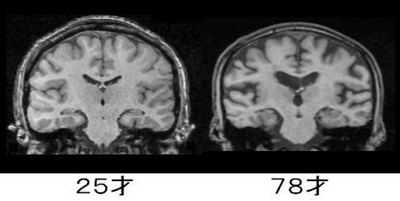

■ MRIから見える“脳の変化”

脳の老化を理解するときに参考になるのが、若年と高齢の脳を比較したMRI画像です。

例えば、25歳と78歳の脳を比べると、次のような違いが確認できます。

- 脳溝(しわ)が深くなり、隙間が広く見える

→ 神経細胞や結合の減少による体積変化の表れ。

- 脳室(脳の中心にある空洞)が大きくなる

→ 周囲の脳組織が萎縮すると、相対的に脳室が拡大して見える。

白質(神経細胞同士の連絡路)の変化は視覚的には分かりにくいものの、こちらも加齢の影響を受けます。

白質のつながりが弱くなると、情報処理のスピードが落ちたり、注意の転換がしにくくなったりすることがあります。

上の画像は、25歳と78歳の脳のMRI(冠状断)です。

健康長寿ネット(https://www.tyojyu.or.jp/net/kenkou-tyoju/rouka/nou-keitai.html)のものを使わせていただいています。